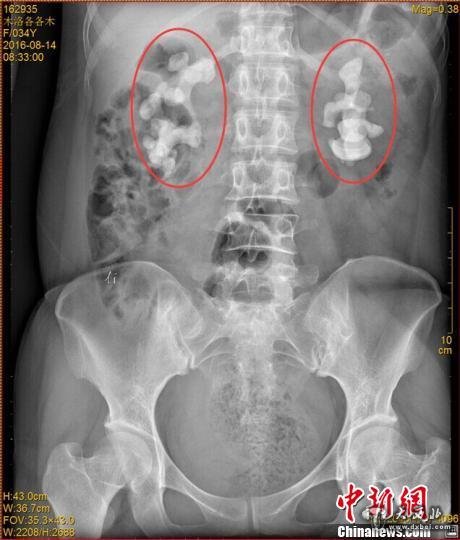

各各木术前影像图片,红圈内为巨大肾结石。 钟欣 摄

中新网成都11月7日电 (王鹏)记者7日从四川省结石病医院获悉,该医院近日收治了一名罕见肾结石病人。来自四川凉山的34岁女子各各木,双肾长出10厘米巨型结石,肾内空间几乎全被结石填满。

“临床上,双肾长巨大结石的患者一般都是中老年男性,女性较为少见,年轻女性更加罕见。”四川省结石病医院常立高医生详细检查后发现,该女子双肾内空间几乎被结石全部填满。他询问患者后判断,该罕见病例的出现与女子常年喝生水有直接关系。

记者了解到,由于各各木肾脏内部几乎全被结石填满,常规的开放式手术并不适用。医院目前已对其进行了4次难度颇高的微创手术,且在进一步观察治疗当中。